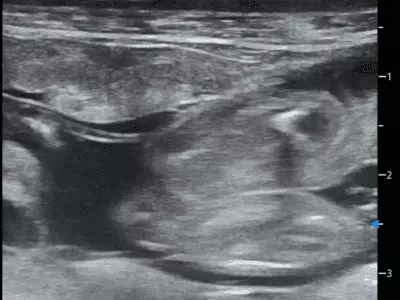

W tym wydaniu m.in: problemy trawienne, dermatozy psychogenne psów, przepuklina brzuszna pępkowa zewnętrzna, szpiczak mnogi, starszy pies z objawami krwioplucia, przegląd objawów behawioralnych w kontekście różnych chorób.